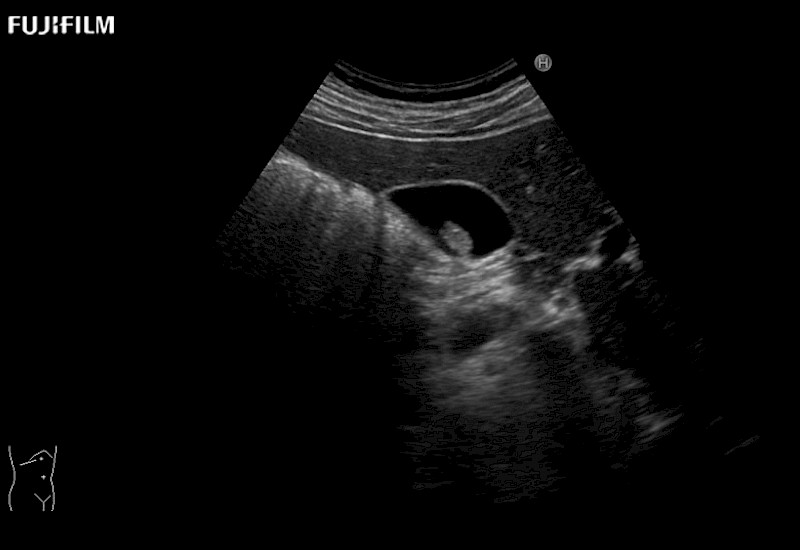

for use during open and laparoscopic procedures: Tumor localization & staging, Ablation, Resection, Biopsy, Transplant, Abdominal exploration, Robotic surgery

Curved array deep penetration “T” style finger-grip transducer for open surgical procedures.

Curved array 4-way laparoscopic transducer for better visualization of targeted lesions.